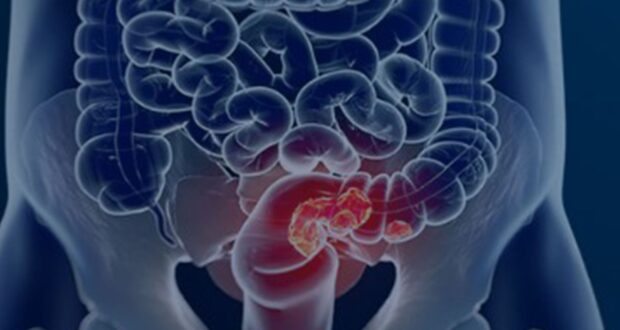

Março azul é o mês dedicado à conscientização e prevenção do câncer colorretal, um tipo de tumor que afeta o intestino grosso e o reto. Anualmente, a campanha busca dissipar mitos e incentivar o diagnóstico precoce, fundamental para o sucesso do tratamento. Estimativas do Instituto Nacional de Câncer (Inca) revelam um cenário preocupante para o Brasil, com cerca de 54 mil novos casos esperados a cada ano até 2028. Apesar de sua prevalência e impacto, o câncer colorretal é um dos tipos mais reversíveis, desde que identificado em estágios iniciais, o que sublinha a urgência da informação e da ação preventiva. A doença, que frequentemente se origina de pequenas lesões benignas, conhecidas como pólipos, exige vigilância constante e o entendimento de seus sinais silenciosos.

O câncer colorretal é uma enfermidade que atinge uma parte vital do sistema digestório: o intestino grosso (cólon) e o reto. Geralmente, ele tem início a partir de lesões pré-cancerígenas, chamadas pólipos, que se desenvolvem na parede interna desses órgãos. Se não forem detectados e removidos a tempo, esses pólipos podem evoluir para um tumor maligno ao longo de anos. A doença é frequentemente caracterizada por sua natureza silenciosa, o que significa que os sintomas podem ser sutis ou facilmente confundidos com outras condições menos graves, dificultando o diagnóstico em fases iniciais. No entanto, o conhecimento desses sinais é crucial para a busca por auxílio médico.

Apesar de ser o segundo tipo de câncer que mais causa mortes no mundo, o câncer colorretal é, paradoxalmente, um dos mais reversíveis quando detectado precocemente. As chances de cura são substancialmente maiores quando a doença é identificada em seus estágios iniciais, muitas vezes antes mesmo do surgimento de sintomas graves. A ferramenta mais eficaz e amplamente recomendada para a detecção precoce é a colonoscopia. Este exame permite não apenas identificar a presença de tumores, mas também localizar e remover pólipos, que são as lesões benignas que podem se transformar em câncer. A remoção de pólipos durante a colonoscopia é uma medida preventiva de alta eficácia, impedindo que a doença sequer se instale. No entanto, a realização desse exame ainda enfrenta barreiras significativas na população.